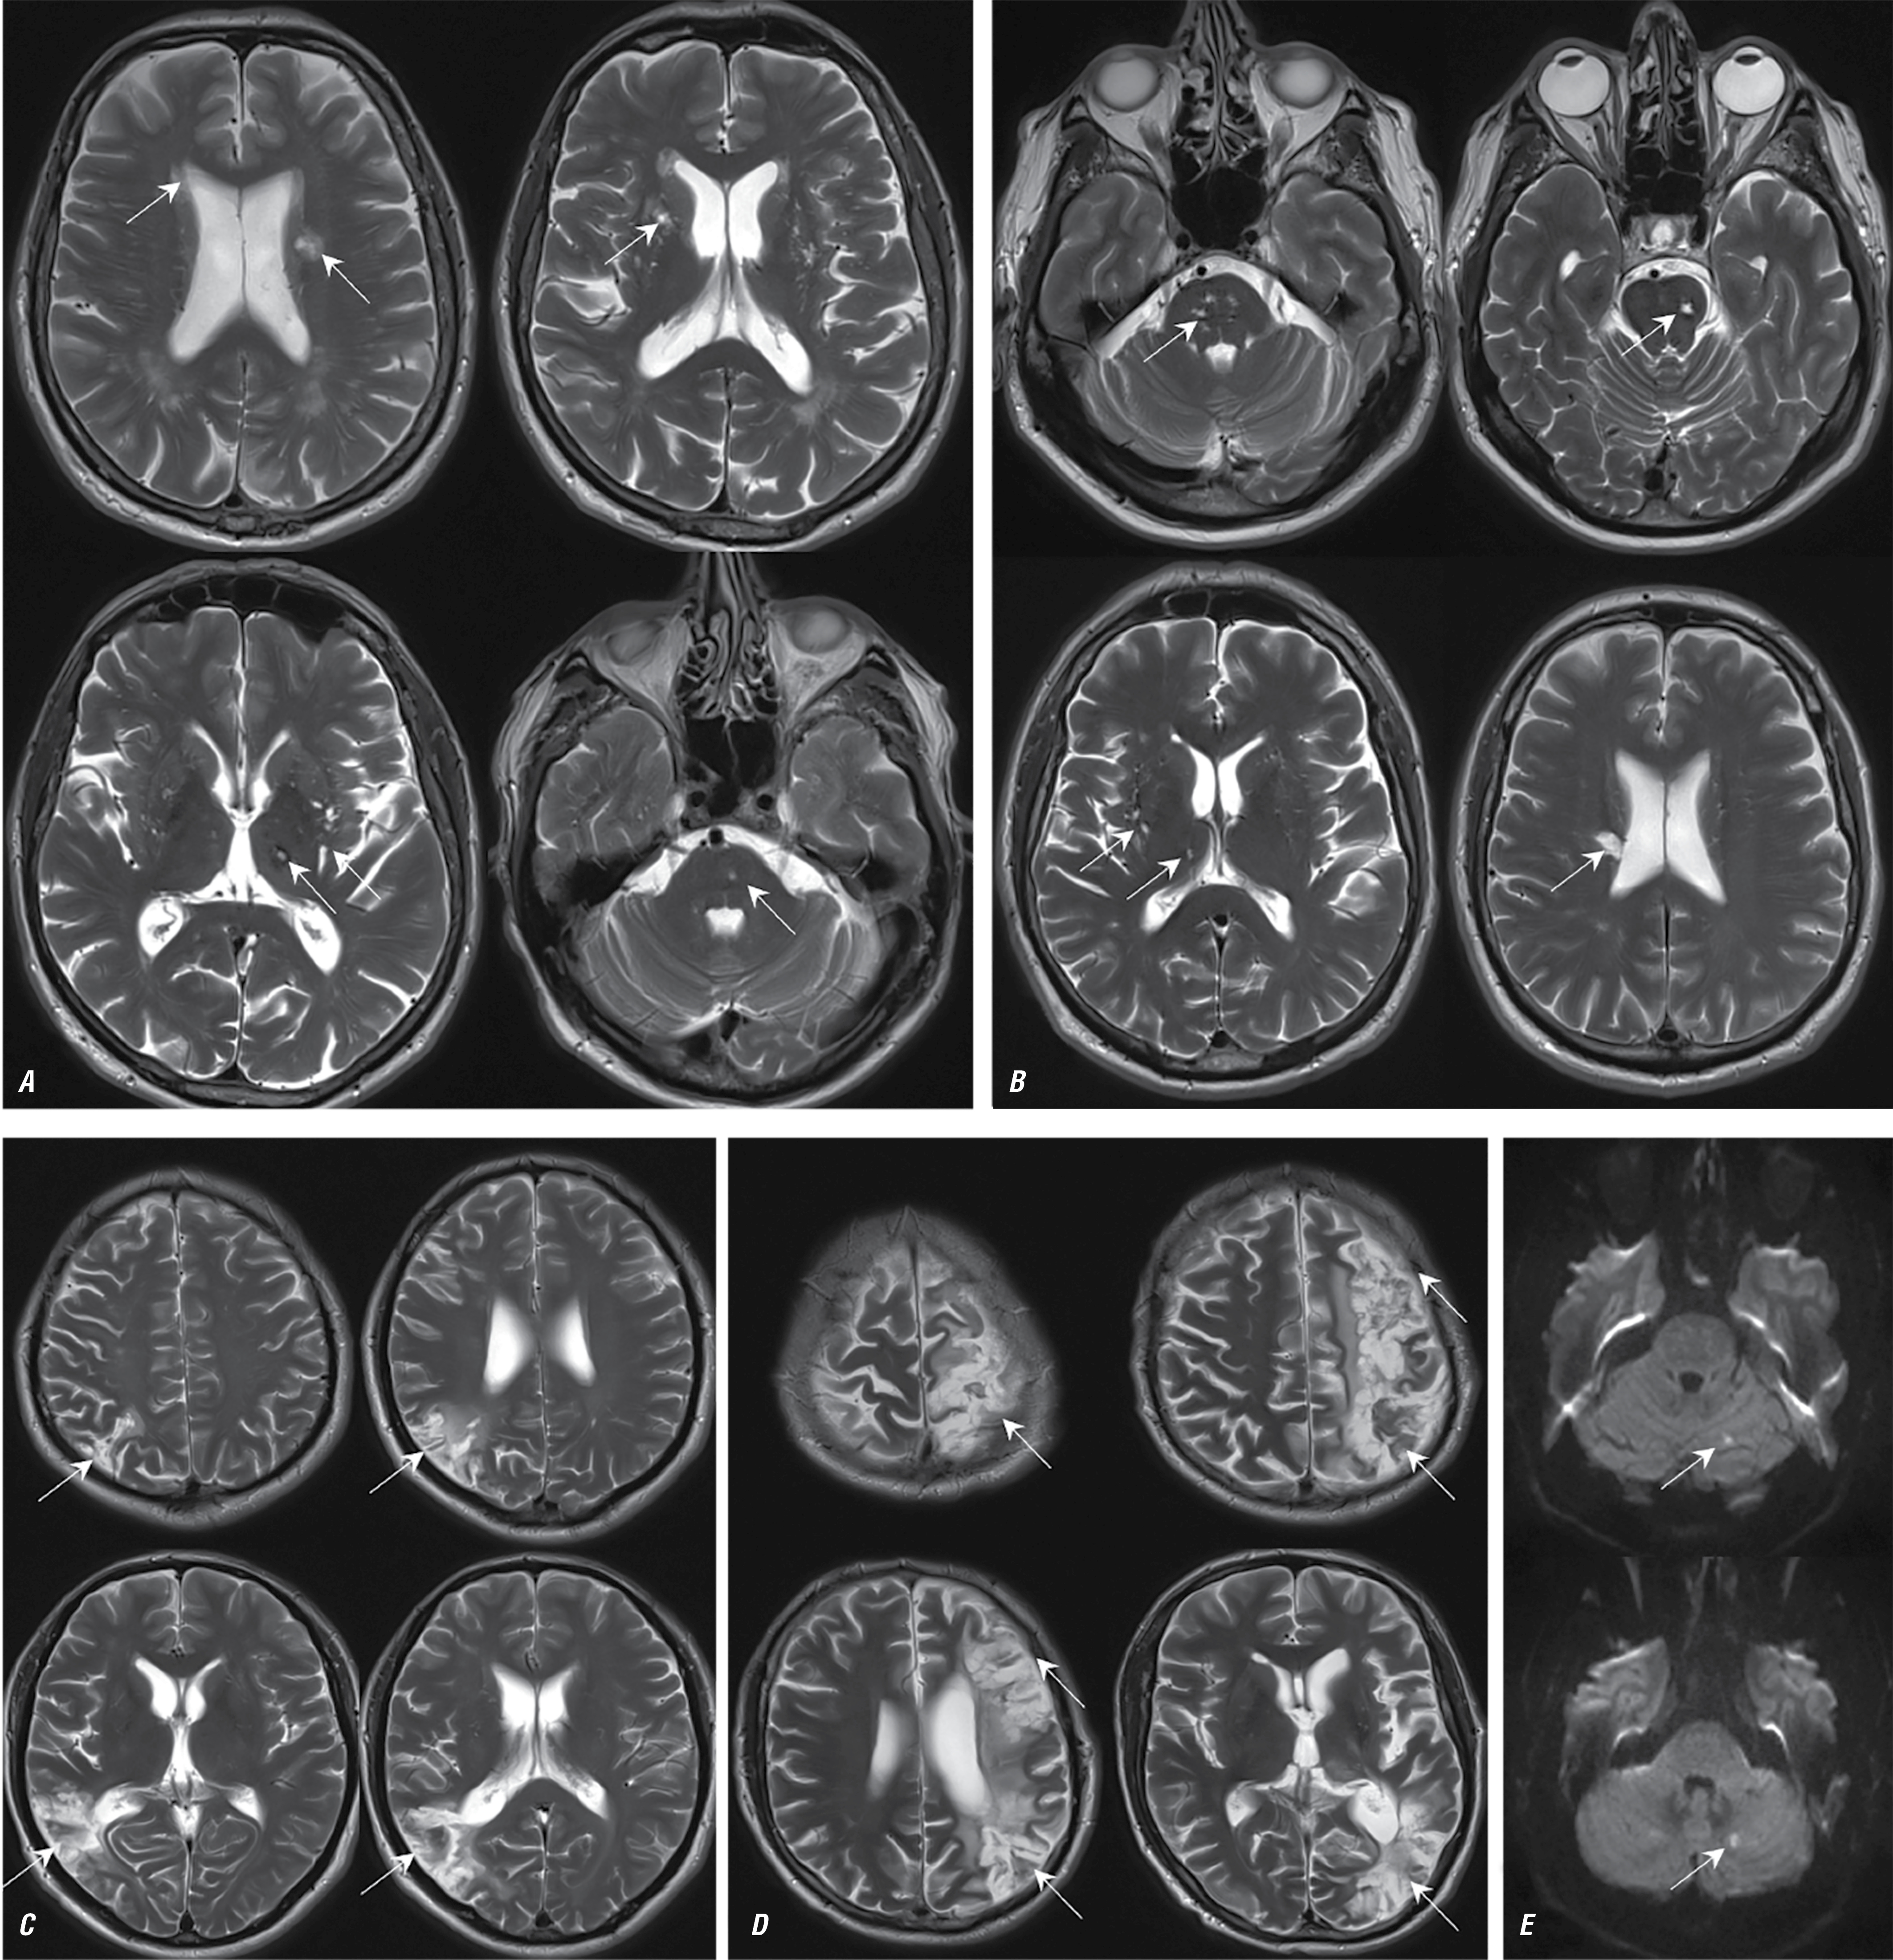

Рис. 4. МРТ головного мозга пациентов с ЭТ — Т2-взвешенные изображения в аксиальной плоскости.

Во всех случаях визуализируются массивные постинфарктные изменения с вовлечением коры, подлежащего и глубокого белого вещества, а также базальных ганглиев (постинфарктные изменения указаны стрелками).

Fig. 4. Brain MRI of patients with ET; axial plane T2-weighted images.

In all cases, massive post-infarction changes are found in the cortex, underlying and deep white matter, and basal ganglia (post-infarction changes are indicated by arrows).

Эссенциальная тромбоцитемия

Характерными нейровизуализационными признаками НМК при ЭТ являлись массивные постинфарктные изменения с вовлечением коры, подлежащего и глубокого белого вещества, базальных ганглиев с частотой встречаемости 67%. В 26% случаев НМК развивалось на фоне тромботической окклюзии внутренней сонной артерии с последующим формированием массивного очага ишемии в веществе мозга. В большинстве случаев клиническая картина была представлена острым началом с развитием грубого неврологического дефицита. В 26% случаев постинфарктные изменения в веществе головного мозга встречались в бассейне вертебрально-базилярной системы, в 74% — в каротидном бассейне. В 33% случаев последствия НМК привели к развитию стойкой утраты дееспособности и инвалидности (средний возраст пациентов — 32 года).

Ведущим нейровизуализационным паттерном последствий НМК при ЭТ был большой объём поражения вещества мозга с корково-подкорковой локализацией (рис. 4).